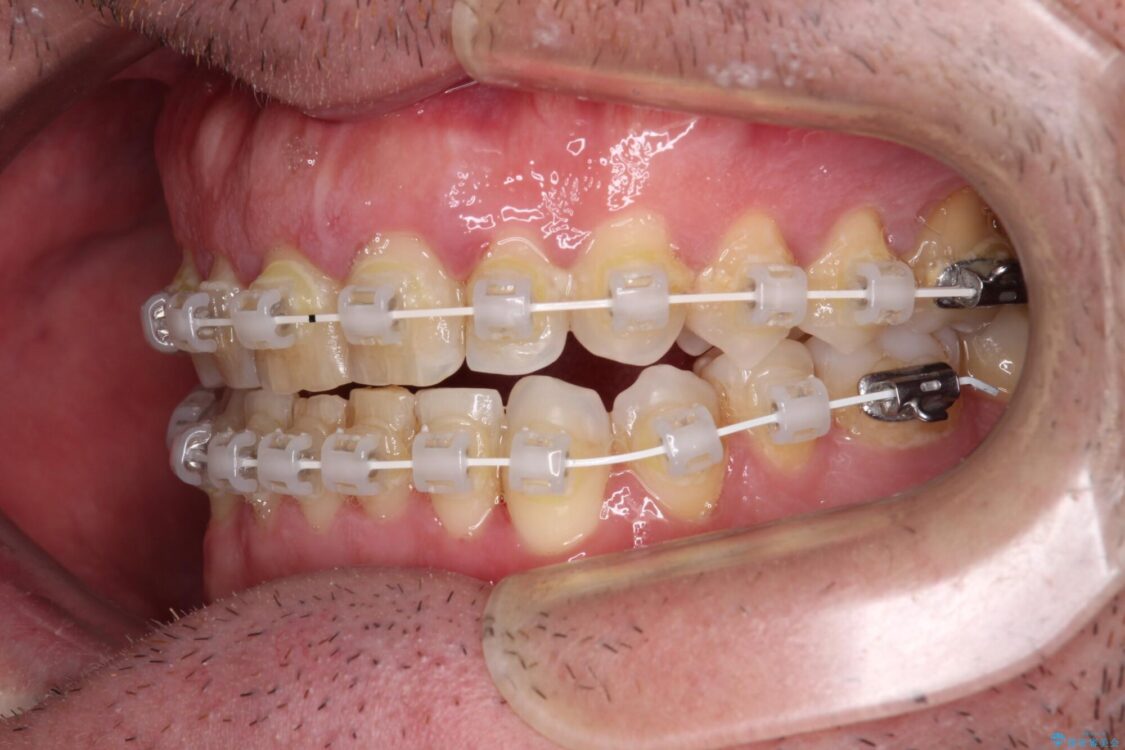

治療途中

• 前歯でものを噛みきりたい 目立たない装置でのワイヤー矯正 治療途中画像